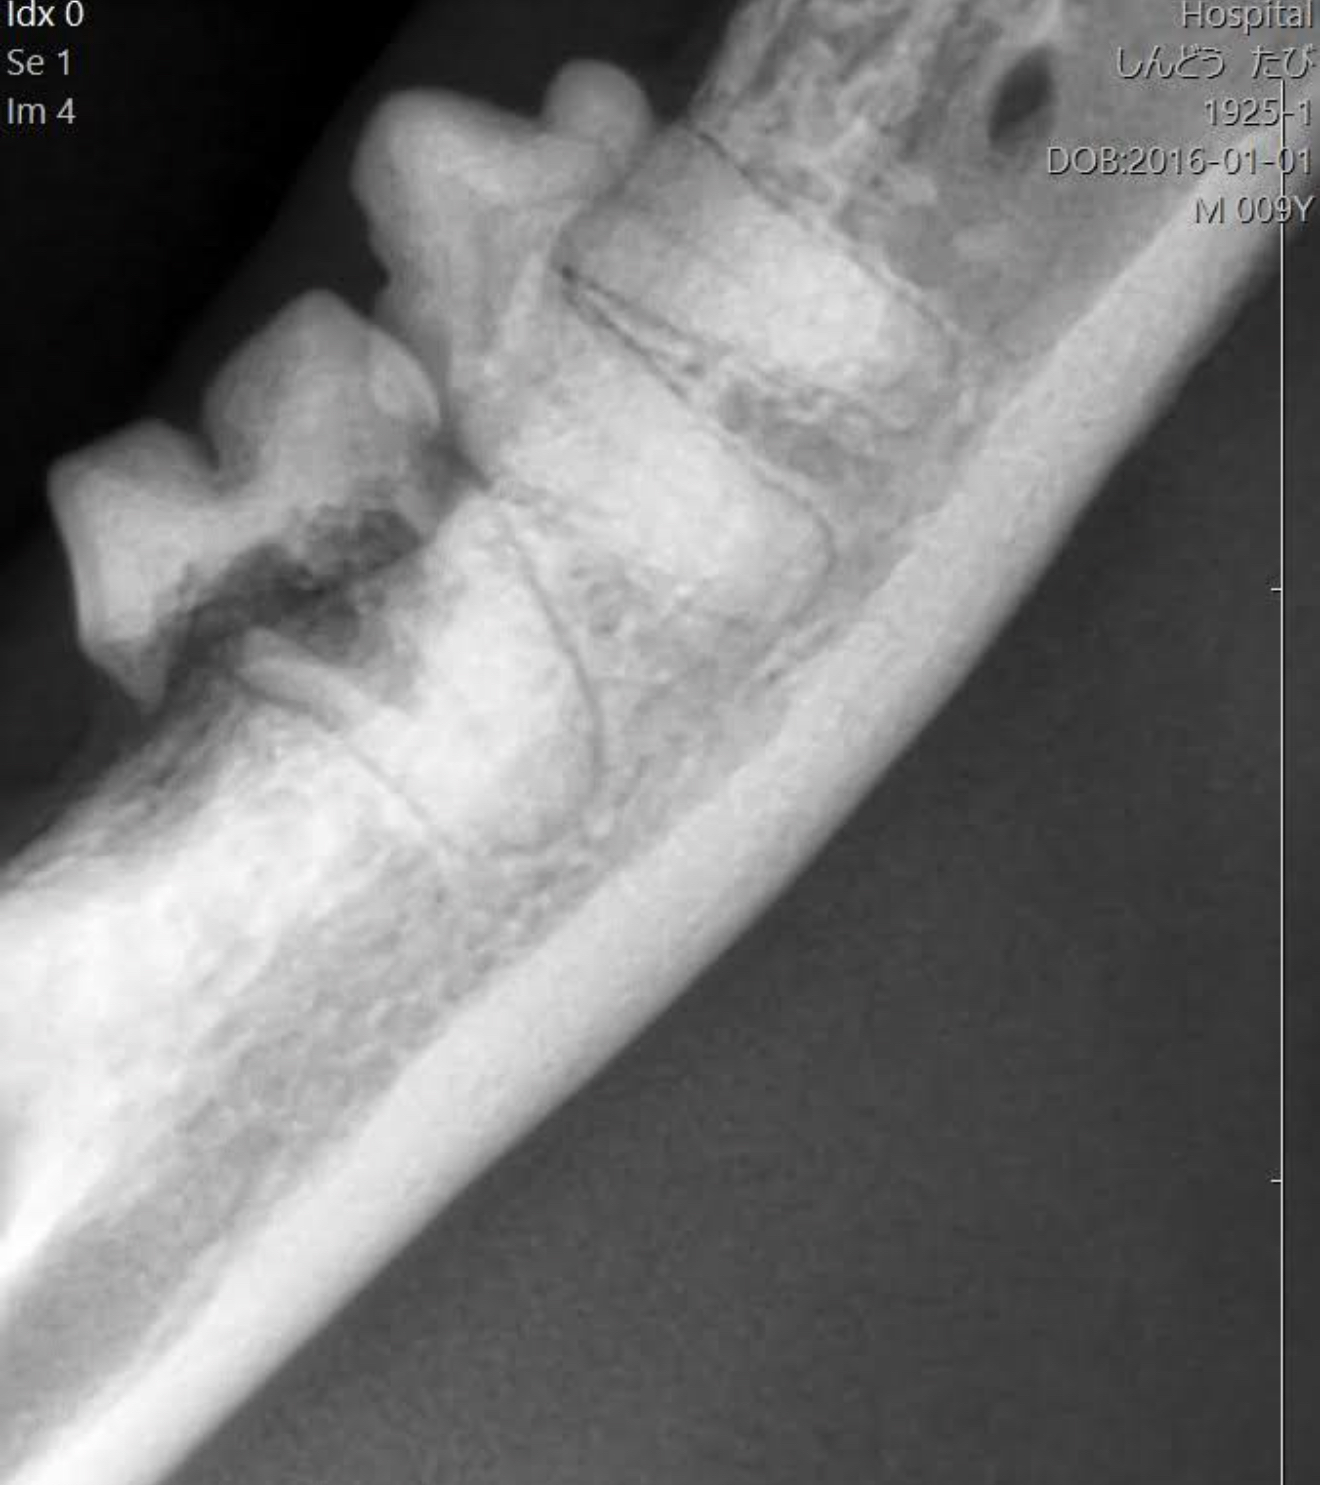

猫の下の奥歯も

コレは右が喉に向かう方

コレは左が喉に向かう方で

反対側の顎になります。

上のレントゲンで一番右の歯が

吸収病巣になっています。

この歯は、抜く必要があり、抜ける歯です。